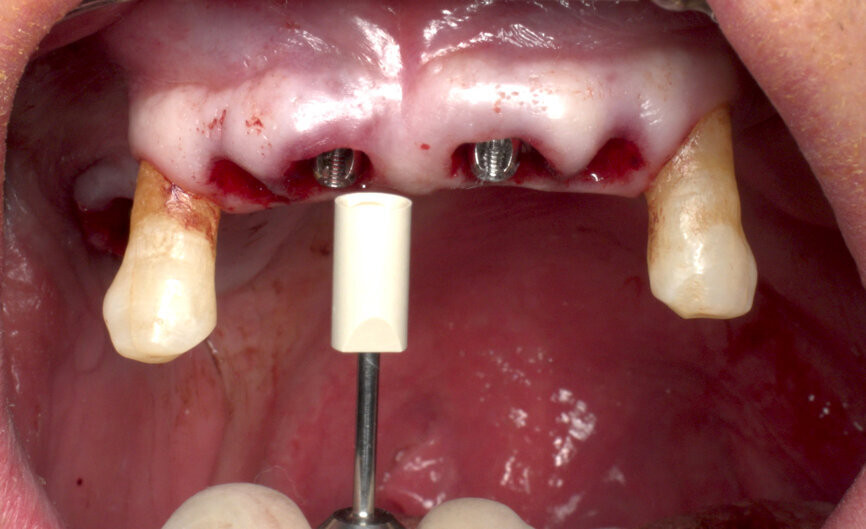

SRAs were connected to all of the implants: two 17º Type A angulated SRAs were placed on the anterior implants to correct the angulation for immediate prosthetic rehabilitation. Straight SRAs were placed on the remaining implants (Fig. 9). New ISQ levels were measured at abutment level using the convenient BLT Type 25 SmartPegs. It is important to record the ISQ level at implant and abutment level in the surgery so that the values can be extrapolated in future Osstell readings at SRA level.

To obtain the final intra-oral surface scan, original Straumann SRA scan bodies were connected to the SRAs under visual control (Fig. 10). A new intra-oral scan was taken to record the patient’s current oral situation, showing the scan bodies and the preserved strategic teeth. This file (File 2) was also sent to the laboratory (Figs. 11 & 12). When the laboratory confirmed receipt of both files, the preserved teeth were extracted and healing caps placed on the abutments, completing the surgery.